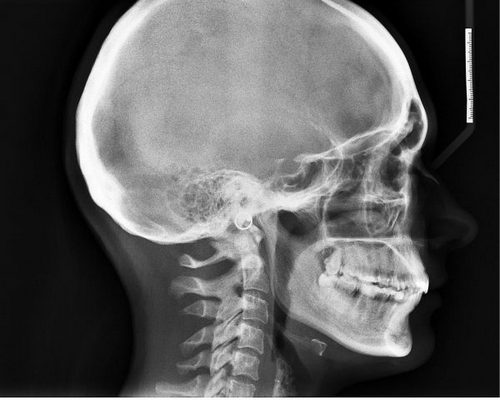

Безусловно, перед началом лечения крайне важно пройти профессиональную диагностику. С ее помощью удастся точно выяснить, с чем именно приходится иметь дело. Не стоит самостоятельно принимать медикаменты, потому как они могут оказаться неэффективны. Курс лечения должен быть назначен в зависимости от ситуации. Например, врач может направить пациента на МРТ и КТ. Эти исследования являются достаточно информативными и позволяют выявить многие патологии мозга. Также нередко назначают рентген, он особенно полезен в случае травм головы.

Болит голова когда встаешь и идешьБезусловно, перед началом лечения крайне важно пройти профессиональную диагностику. С ее помощью удастся точно выяснить, с чем именно приходится иметь дело. Не стоит самостоятельно принимать медикаменты, потому как они могут оказаться неэффективны. Курс лечения должен быть назначен в зависимости от ситуации. Например, врач может направить пациента на МРТ и КТ. Эти исследования являются достаточно информативными и позволяют выявить многие патологии мозга. Также нередко назначают рентген, он особенно полезен в случае травм головы.